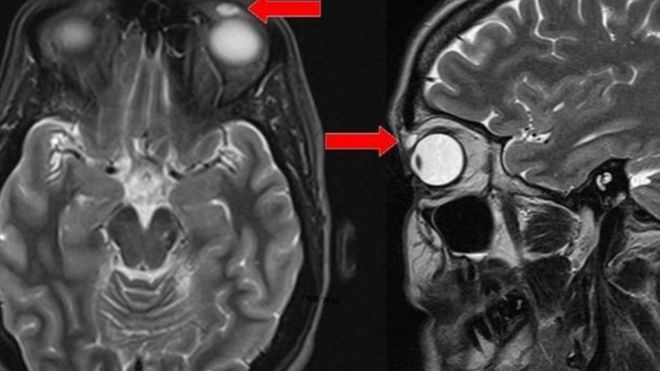

وكشفت صور الآشعة عن وجود كيس بيضاوي الشكل يبلغ طوله 8 ملليمترات، لكن ليست هناك أدلة على وجود أي شيء داخله. وعندما أزيلت الكتلة المتورمة، تمزق الكيس ليكشف عن وجود العدسة.